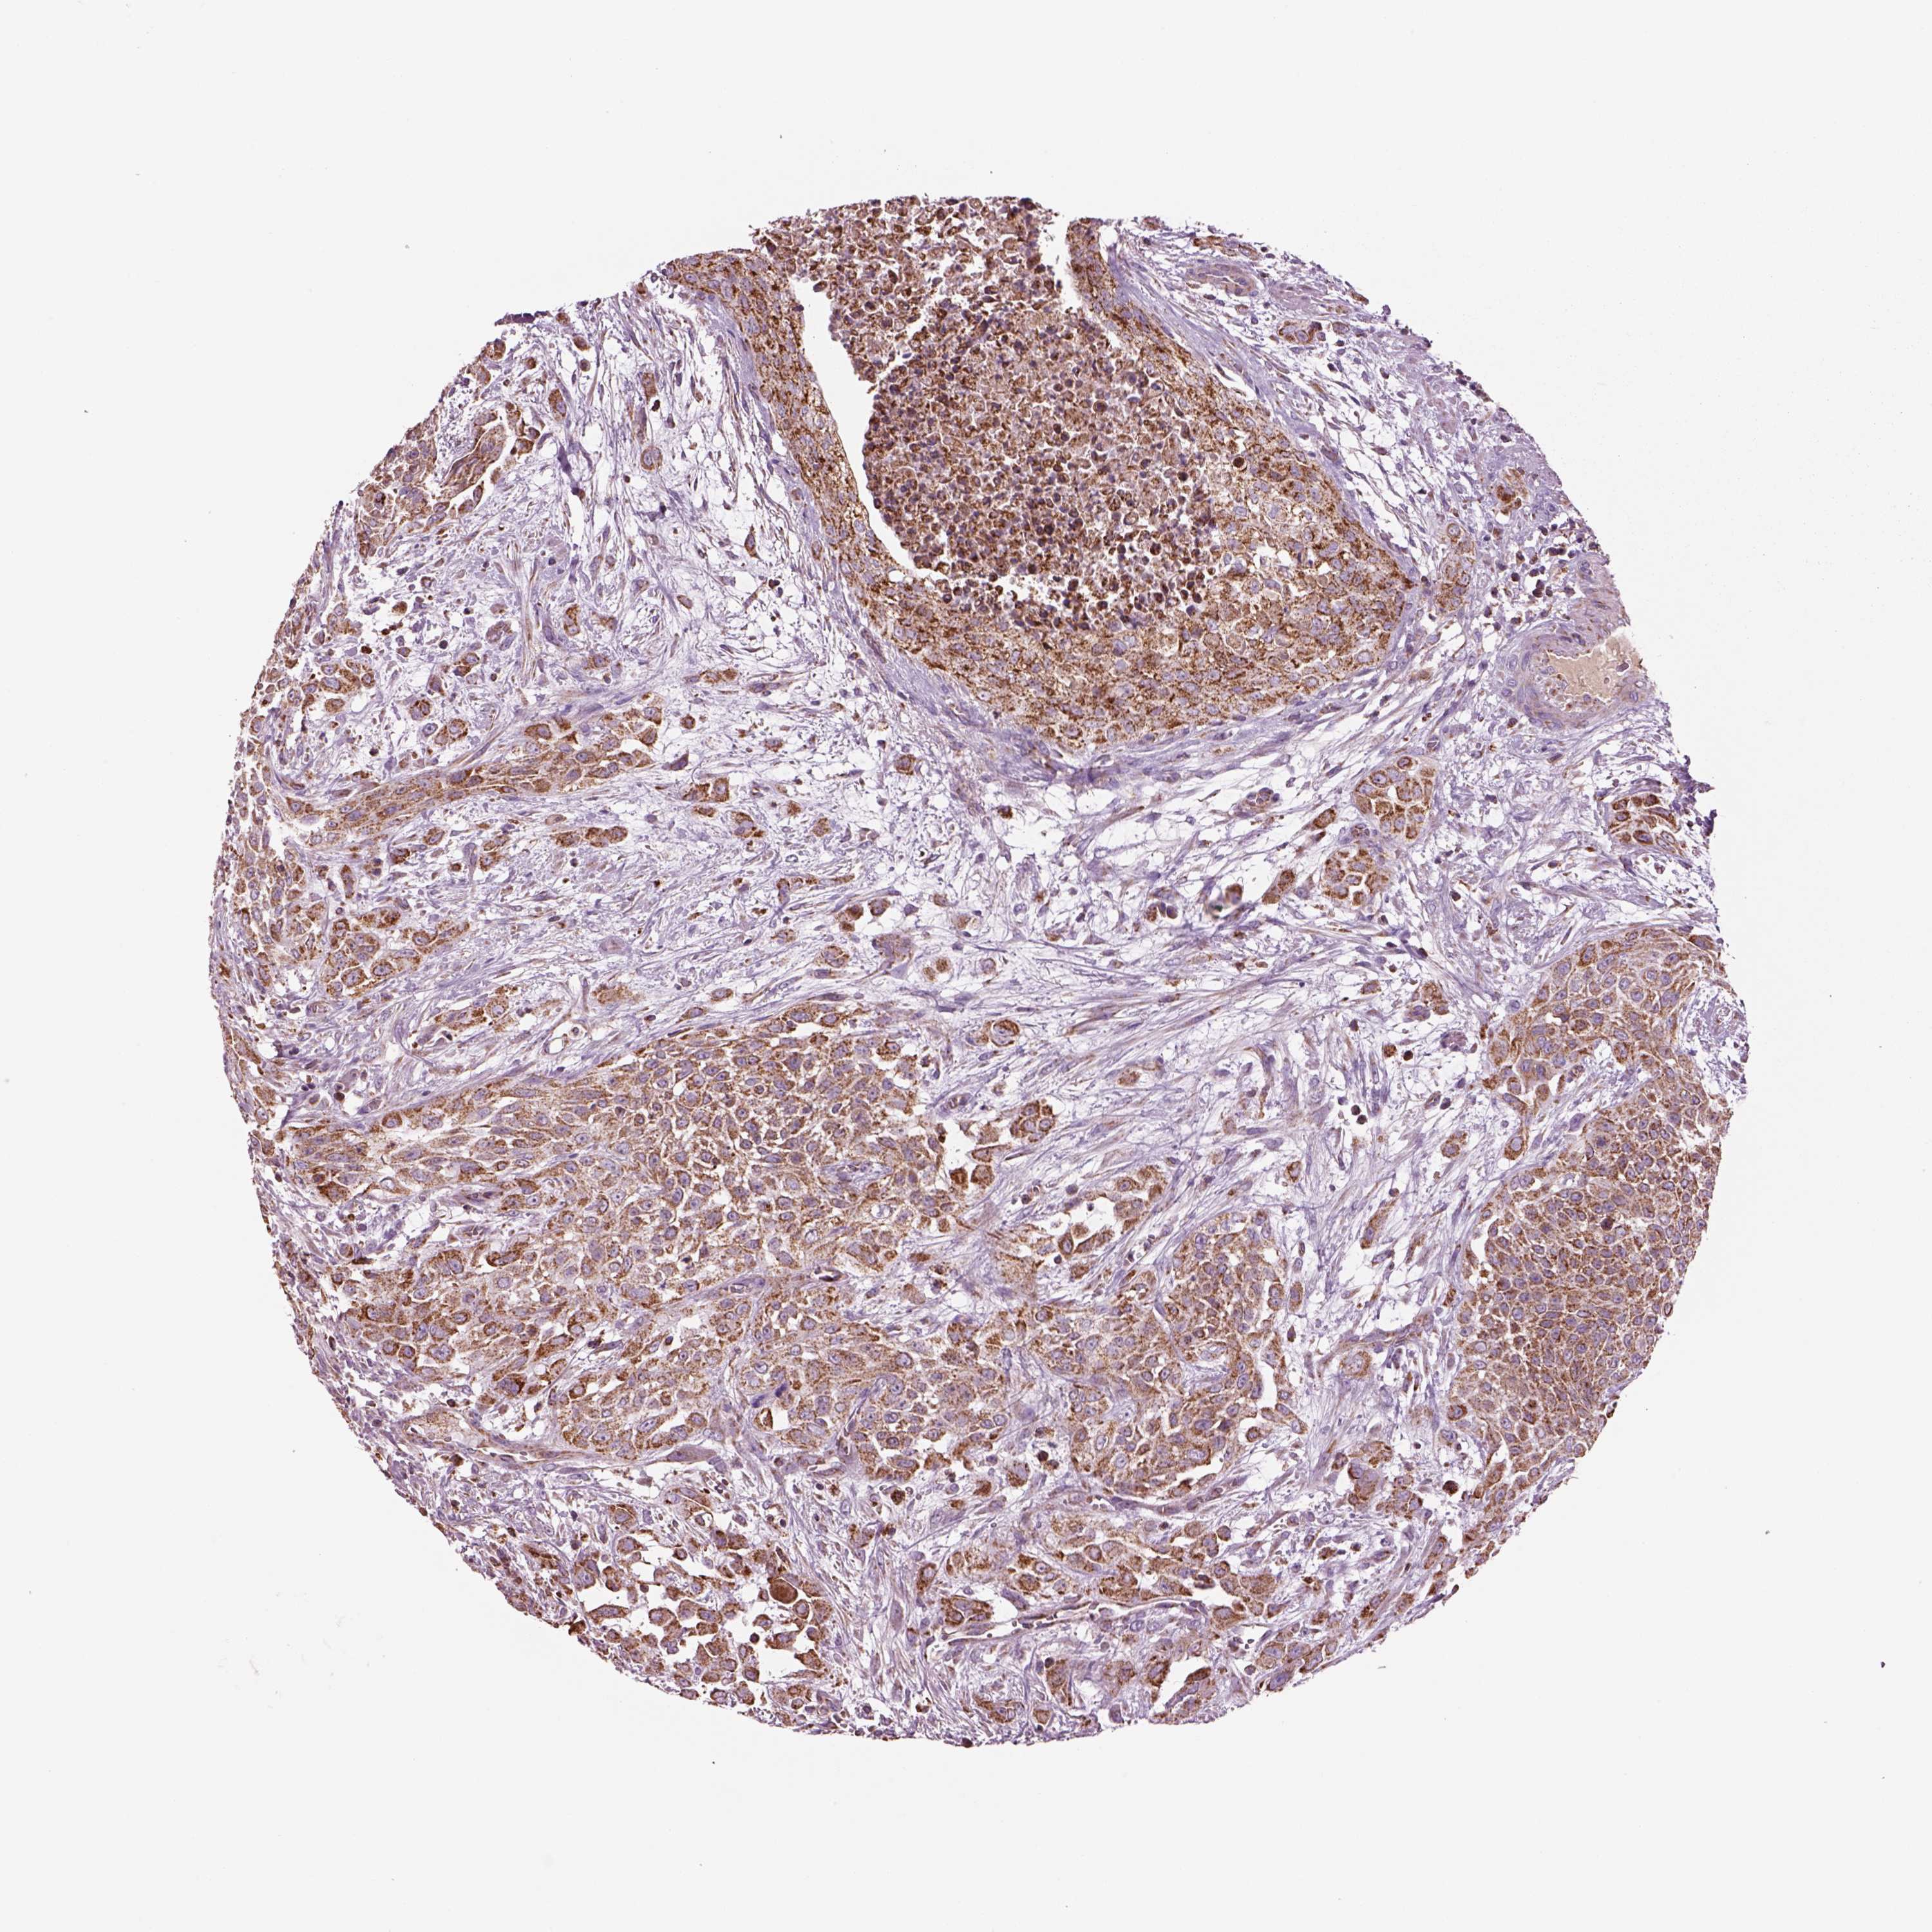

UROTHELIAL CANCER - Protein expressioni

A mouse-over function shows sample information and annotation data. Click on an image to view it in a full screen mode. Samples can be filtered based on level of antibody staining by selecting one or several of the following categories: high, medium, low and not detected. The assay and annotation is described here.

Note that samples used for immunohistochemistry by the Human Protein Atlas do not correspond to samples in the TCGA dataset.

Antibody stainingi

Antibody staining in the annotated cell types in the current human tissue is reported as not detected, low, medium, or high, based on conventional immunohistochemistry profiling in selected tissues. This score is based on the combination of the staining intensity and fraction of stained cells.

Each image is clickable and will lead to virtual microscopy that enables deeper exploration of all samples and also displays staining intensity scores, fraction scores and subcellular localization as well as patient and tissue information for each sample.

Antibody HPA063636

Staining

High

Medium

Low

Not detected

Intensity

Strong

Moderate

Weak

Negative

Quantity

>75%

75%-25%

<25%

None

Location

Urothelial carcinoma, High grade

Urothelial carcinoma, NOS

Urothelial carcinoma, Low grade